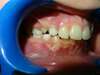

Intrabuccale gauche - Avant traitement 1 (25-01-2021) - 3

Intrabuccale gauche - Fin de traitement (24-09-2023) - 31